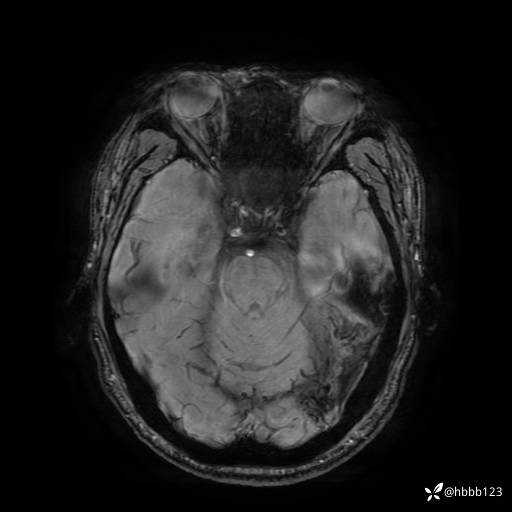

SWAN: